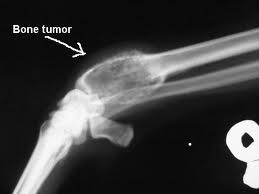

Next, your doctor will likely order some imaging studies. Plain X-rays are often ordered first. In some cases, if the cancer is identified very early, it may not show up on plain X-rays. The appearance of a tumor on the X-ray can help determine the type of cancer and whether or not it is benign or malignant. Benign tumors are more likely to have a smooth border while malignant tumors are more likely to have a ragged border on X-ray images. This is because the benign tumors typically grow more slowly and the bone has time to try to surround the tumor with normal bone. Malignant tumors are more likely to grow more quickly, not giving the normal bone a chance to surround the tumor. The X-rays can also be used to identify if a fracture has occurred or if the bone has been weakened and is at risk for a potential fracture.